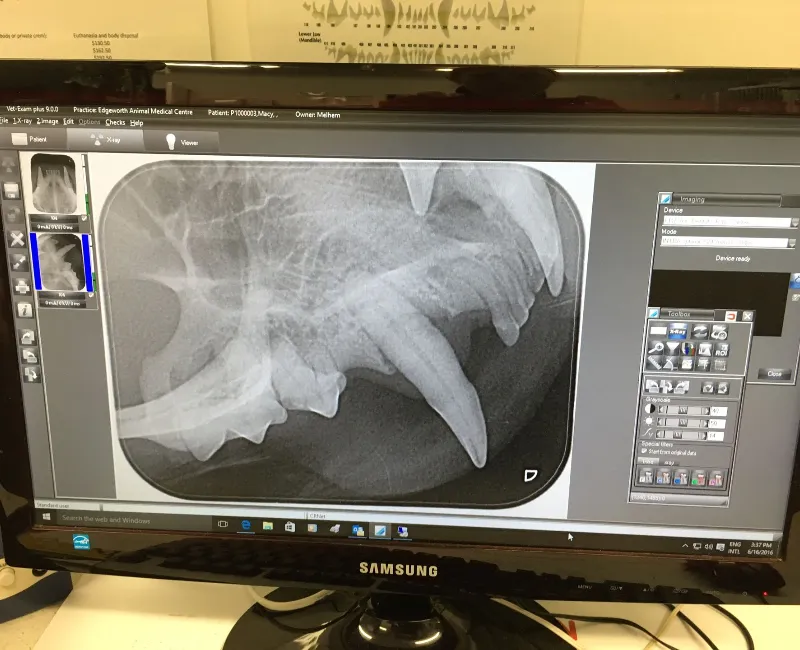

Treatment involves general anaesthesia, dental X-rays, and tooth assessment. We remove any diseased teeth. While under anaesthesia, we remove plaque and tartar and apply protective treatments. Post-operative home care is necessary. Regular brushing, gels, chews, and dental diets will help maintain oral health.

It includes anaesthesia, X-rays, plaque/tartar removal, tooth extractions if needed, and thorough monitoring for safety.